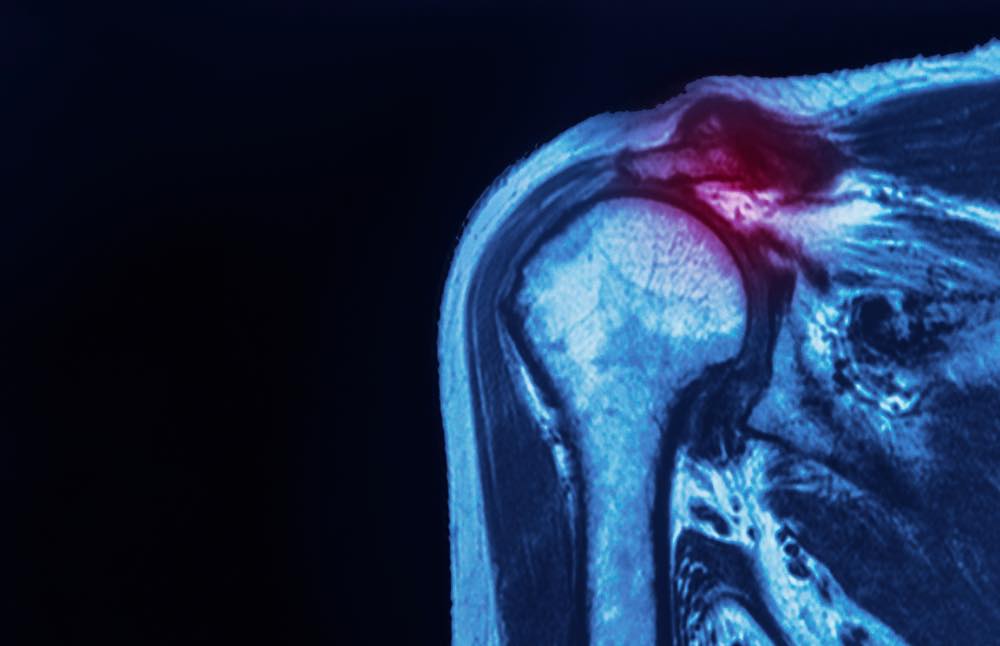

肩 旋 轉 肌 腱 (Rotator cuff) 是 在 肩 關 節 中 由 棘 上 肌 (Supraspinatus) , 棘 下 肌 (Infraspinatus),肩胛下肌(subscapularis)和小圓肌(Teres minor) 四條連接肩胛骨和 肱骨的肌肉群組成,讓手臂可做上舉、丟擲、推拉、旋轉和伸前動作,而最易受傷的 肌肉為棘上肌(Supraspinatus) ,即所謂的肩旋轉肌腱炎。)圖一跟圖二為卡通圖

肩旋轉肌是一組四個肌肉及其圍繞肩關節的肌腱,並將肩胛骨連接到上臂骨。而滑囊是關節附近的小囊,提供潤滑液,減少骨骼、肌腱和韌帶之間的摩擦。當肩旋轉肌過度使用時會導致肩旋轉肌問題,包括肌腱炎,張力以及肌腱的部分和完全撕裂。